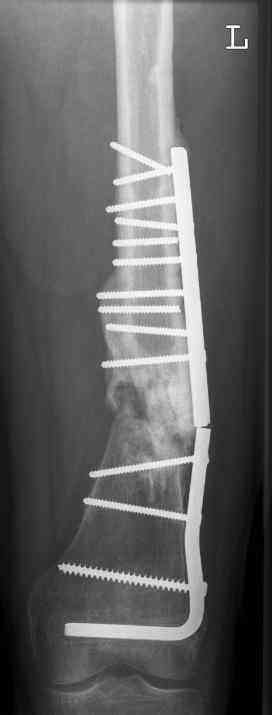

16 yr old boy, high energy motorcycle trauma trauma in July 2005 with:

- hip dislocation + acetabular fracture L

- distal femoral fracture L

- tibial shaft fracture L

- metatarsal fractures L

july 05: LISS femur, LCP plate tibia, double recon. plate post. acetabulum

oct 05: cancellous bone graft femur

aug 06: blade plate + bone graft

nov 06: revision blade plate

feb 07: retrograde nail + bone graft + BMP

may 07: dynamisation nail

sept 07: locking screw removal (max. dynamisation reached)

nov 07: persistant non-union distal femur; other fractures healed uneventfully.